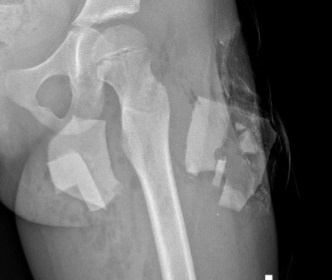

Ngay sau khi vào viện, bệnh nhân được khám, sơ cứu cầm máu vết thương và chụp phim X-quang. Phim chụp phát hiện có đa dị vật cản quang đầu trên đùi trái và cẳng chân phải. Bệnh nhân được chỉ định phẫu thuật cấp cứu xử trí vết thương lấy dị vật.

Phim chụp phát hiện có đa dị vật cản quang đầu trên đùi trái và cẳng chân phải. Ảnh: BVCC.

Quá trình mổ, các bác sĩ phát hiện dị vật là mảnh sành xuyên từ mặt ngoài đùi trái, đi giữa lớp cơ thẳng đùi vào đến vùng dưới bẹn nơi có bó mạch thần kinh đi qua. Dị vật gãy làm đôi, một mảnh ở phía ngoài vết thương, còn một mảnh nằm sâu bên trong, để lại đường hầm nằm dưới lớp cơ.

Đặc biệt, mảnh dị vật ở phía trong, nằm sát ngay bên cạnh bó mạch thần kinh đùi nhưng chưa gây tổn thương đến bó mạch. Tuy nhiên, việc gắp dị vật ra để không ảnh hưởng đến mạch máu thần kinh của bệnh nhân là điều không hề dễ dàng.